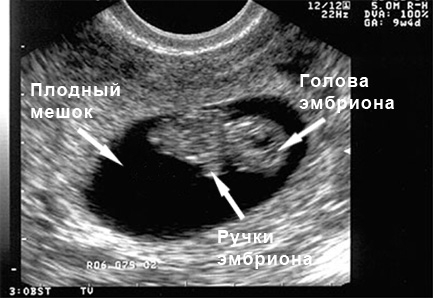

УЗИ: 7-ая неделя беременности

Эмбрион увеличился в размерах в 10 000 раз по сравнению с тем, каким он был в момент зачатия. Сердце продолжает активно развиваться. УЗИ фиксирует частоту сердечных сокращений, которая в норме достигает 160 ударов в минуту. Можно наблюдать, как интенсивно формируются конечности будущего ребенка. В данный момент происходит развитие языка и рта. У эмбриона уже имеются почки, которые выводят мочу, и они состоят из трех частей.

УЗИ: 8-ая неделя беременности

Размер эмбриона составляет около 12-14 миллиметров. Конечности начинают укрепляться и удлиняться. Веки начинают формироваться. Также закладываются уже развитые яичники или яички, в зависимости от пола будущего малыша. Движения эмбриона становятся более заметными.